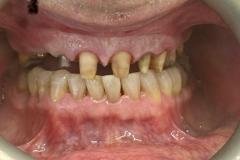

Full smile rehabilitation involving replacement of missing and failing teeth with implant-supported restorations, combined with aesthetic correction of existing dentition. The treatment was carefully planned to restore function, improve alignment, and achieve a balanced, natural-looking smile.

Implants were strategically placed to support long-term stability, with particular attention to soft tissue contours and emergence profiles to ensure seamless integration with the surrounding teeth. The final restoration was designed to enhance both aesthetics and bite function, delivering a confident and harmonious result.

This case demonstrates a comprehensive approach to implant and restorative dentistry, combining surgical precision with advanced prosthetic design to achieve predictable, long-term outcomes.